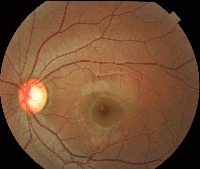

Classes (69)

0.0.Normal

0.1.Tessellated fundus

0.2.Large optic cup

0.3.DR1

1.0.DR2

1.1.DR3

10.0.Possible glaucoma

10.1.Optic atrophy

11.Severe hypertensive retinopathy

12.Disc swelling and elevation

13.Dragged Disc

14.Congenital disc abnormality

15.0.Retinitis pigmentosa

16

17

18

19

2

2.0.BRVO

2.1.CRVO

3.RAO

4.Rhegmatogenous RD

5.0.CSCR

5.1.VKH disease

6.Maculopathy

7.ERM

8.MH

9.Pathological myopia